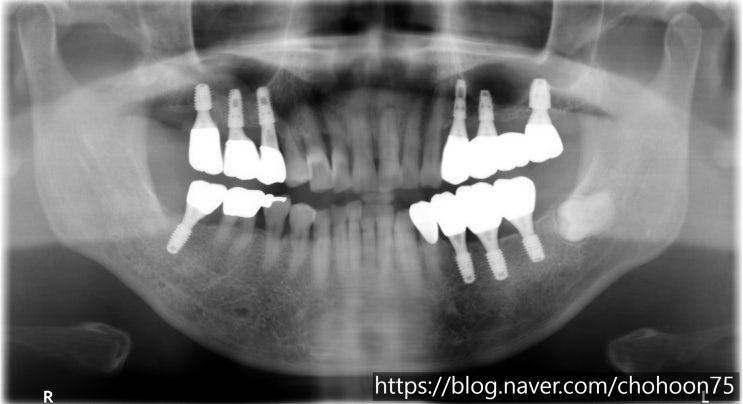

[조훈치과] 다수의 치아 상실 임플란트 치료로 대체

안녕하세요. 조훈 치과입니다. 많은 치아의 임플란트 식립이 필요하다면? 대부분의 치아를 상실하였을 때 ...